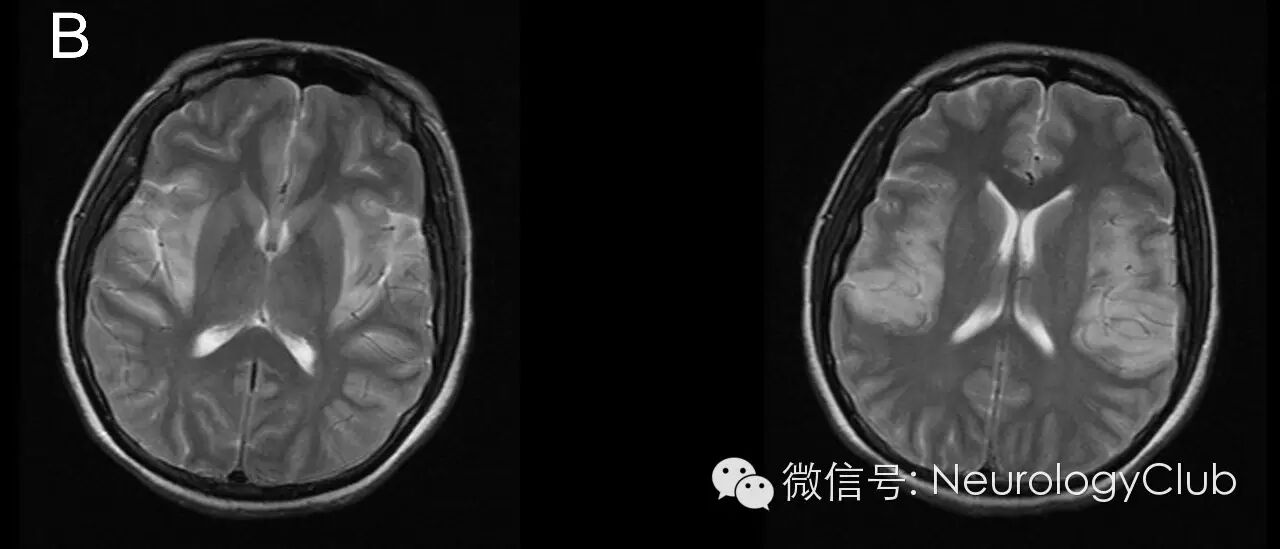

病变侵犯大脑额、颞叶、枕叶及岛叶皮质区,呈T1WI低信号,T2WI/FLAIR高信号,未累及基底节。病变区与豆状核之间边界清楚,凸面向外,如刀切样,称“刀切征”。常见于病毒性脑炎,特别是单纯疱疹病毒性脑炎。罕见于鸟氨酸氨甲酰基转移酶缺乏症等。

患者,女,31岁,主诉“发热伴头痛5天,肢体抽搐1天”

(图1:T1WI)

(图2:T2WI)

在各种病毒所致脑炎中,单纯疱疹病毒性脑炎的影像学最具特征性,可归纳为:①病变多先累及单侧或双侧颞叶,部分病例可向额叶或枕叶发展,单独发生于额叶、枕叶及顶叶者少见;②病变均与豆状核之间界线清楚,凸面向外,如刀切样,称刀切征,许多学者认为这是本病最具特征性的表现;③CT平扫呈片状不规则低密度,,MRI检查呈长T1、T2片状高信号,以T2WI上病变显示最为清楚;④不增强或线样脑回状增强。主要位于病变的边缘部分。增强与否可能与病变的严重程度有关,因为广泛的血管炎和脑组织灶性坏死是出血强化的病理基础;⑤严重者可有占位效应。